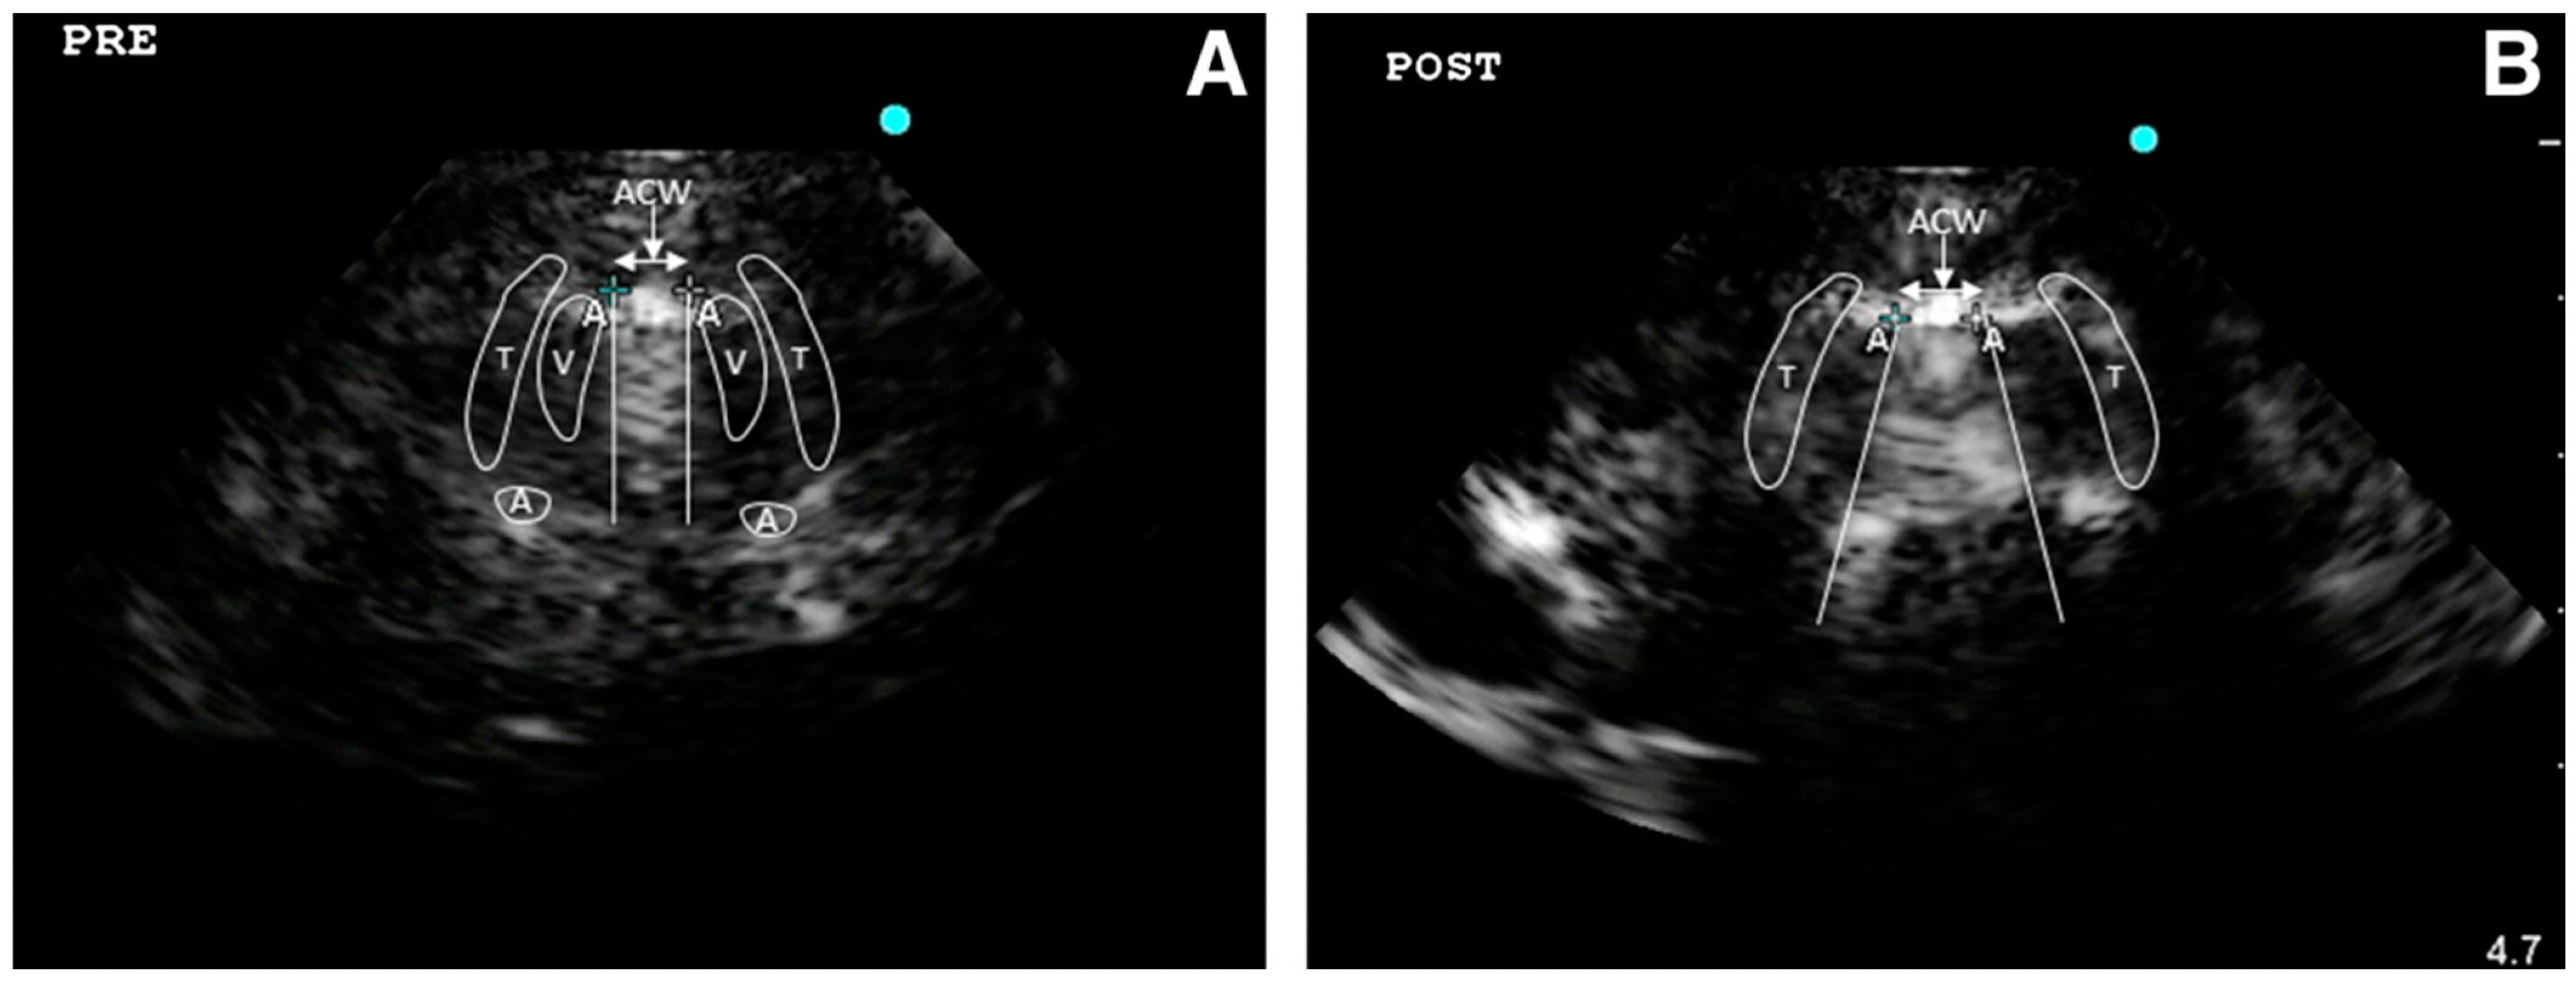

4.2.1. Protocols on Lung US

- -

- Abolition of lung sliding alone, sensitivity 100% specificity 78%;

- Absent lung sliding plus the A-line sign, sensitivity 95% specificity 94%;

- Lung point, sensitivity 79% specificity 100% [35].

Acute Respiratory Distress Syndrome (ARDS)